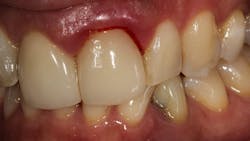

There are a multitude of reasons why patients may not respond properly to periodontal therapy or why their gums still bleed after a dental cleaning (figure 1).1 Of tantamount importance is to discern why previous therapy has not worked prior to reinitiating treatment or simply “giving the patient another cleaning.”